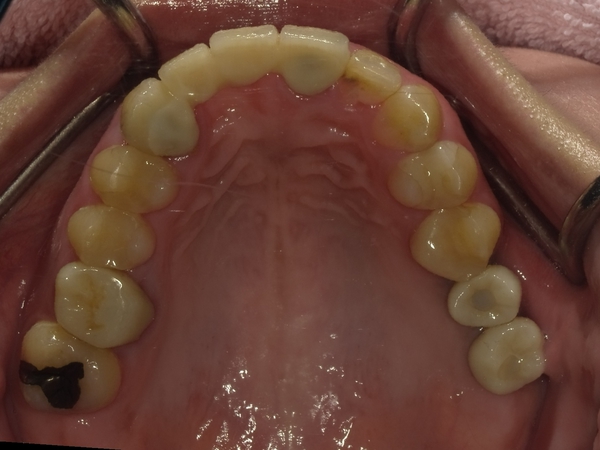

30代女性非抜歯

BEFORE→AFTER

〇ご相談内容:歯の叢生(ガタガタ)

〇矯正の種類:マウスピース型矯正「インビザラインGo」

〇治療期間:16週間

〇治療費用:44万円(税込)